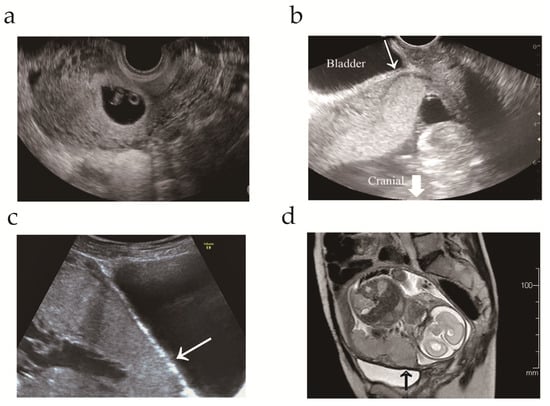

3.1. Case Presentation